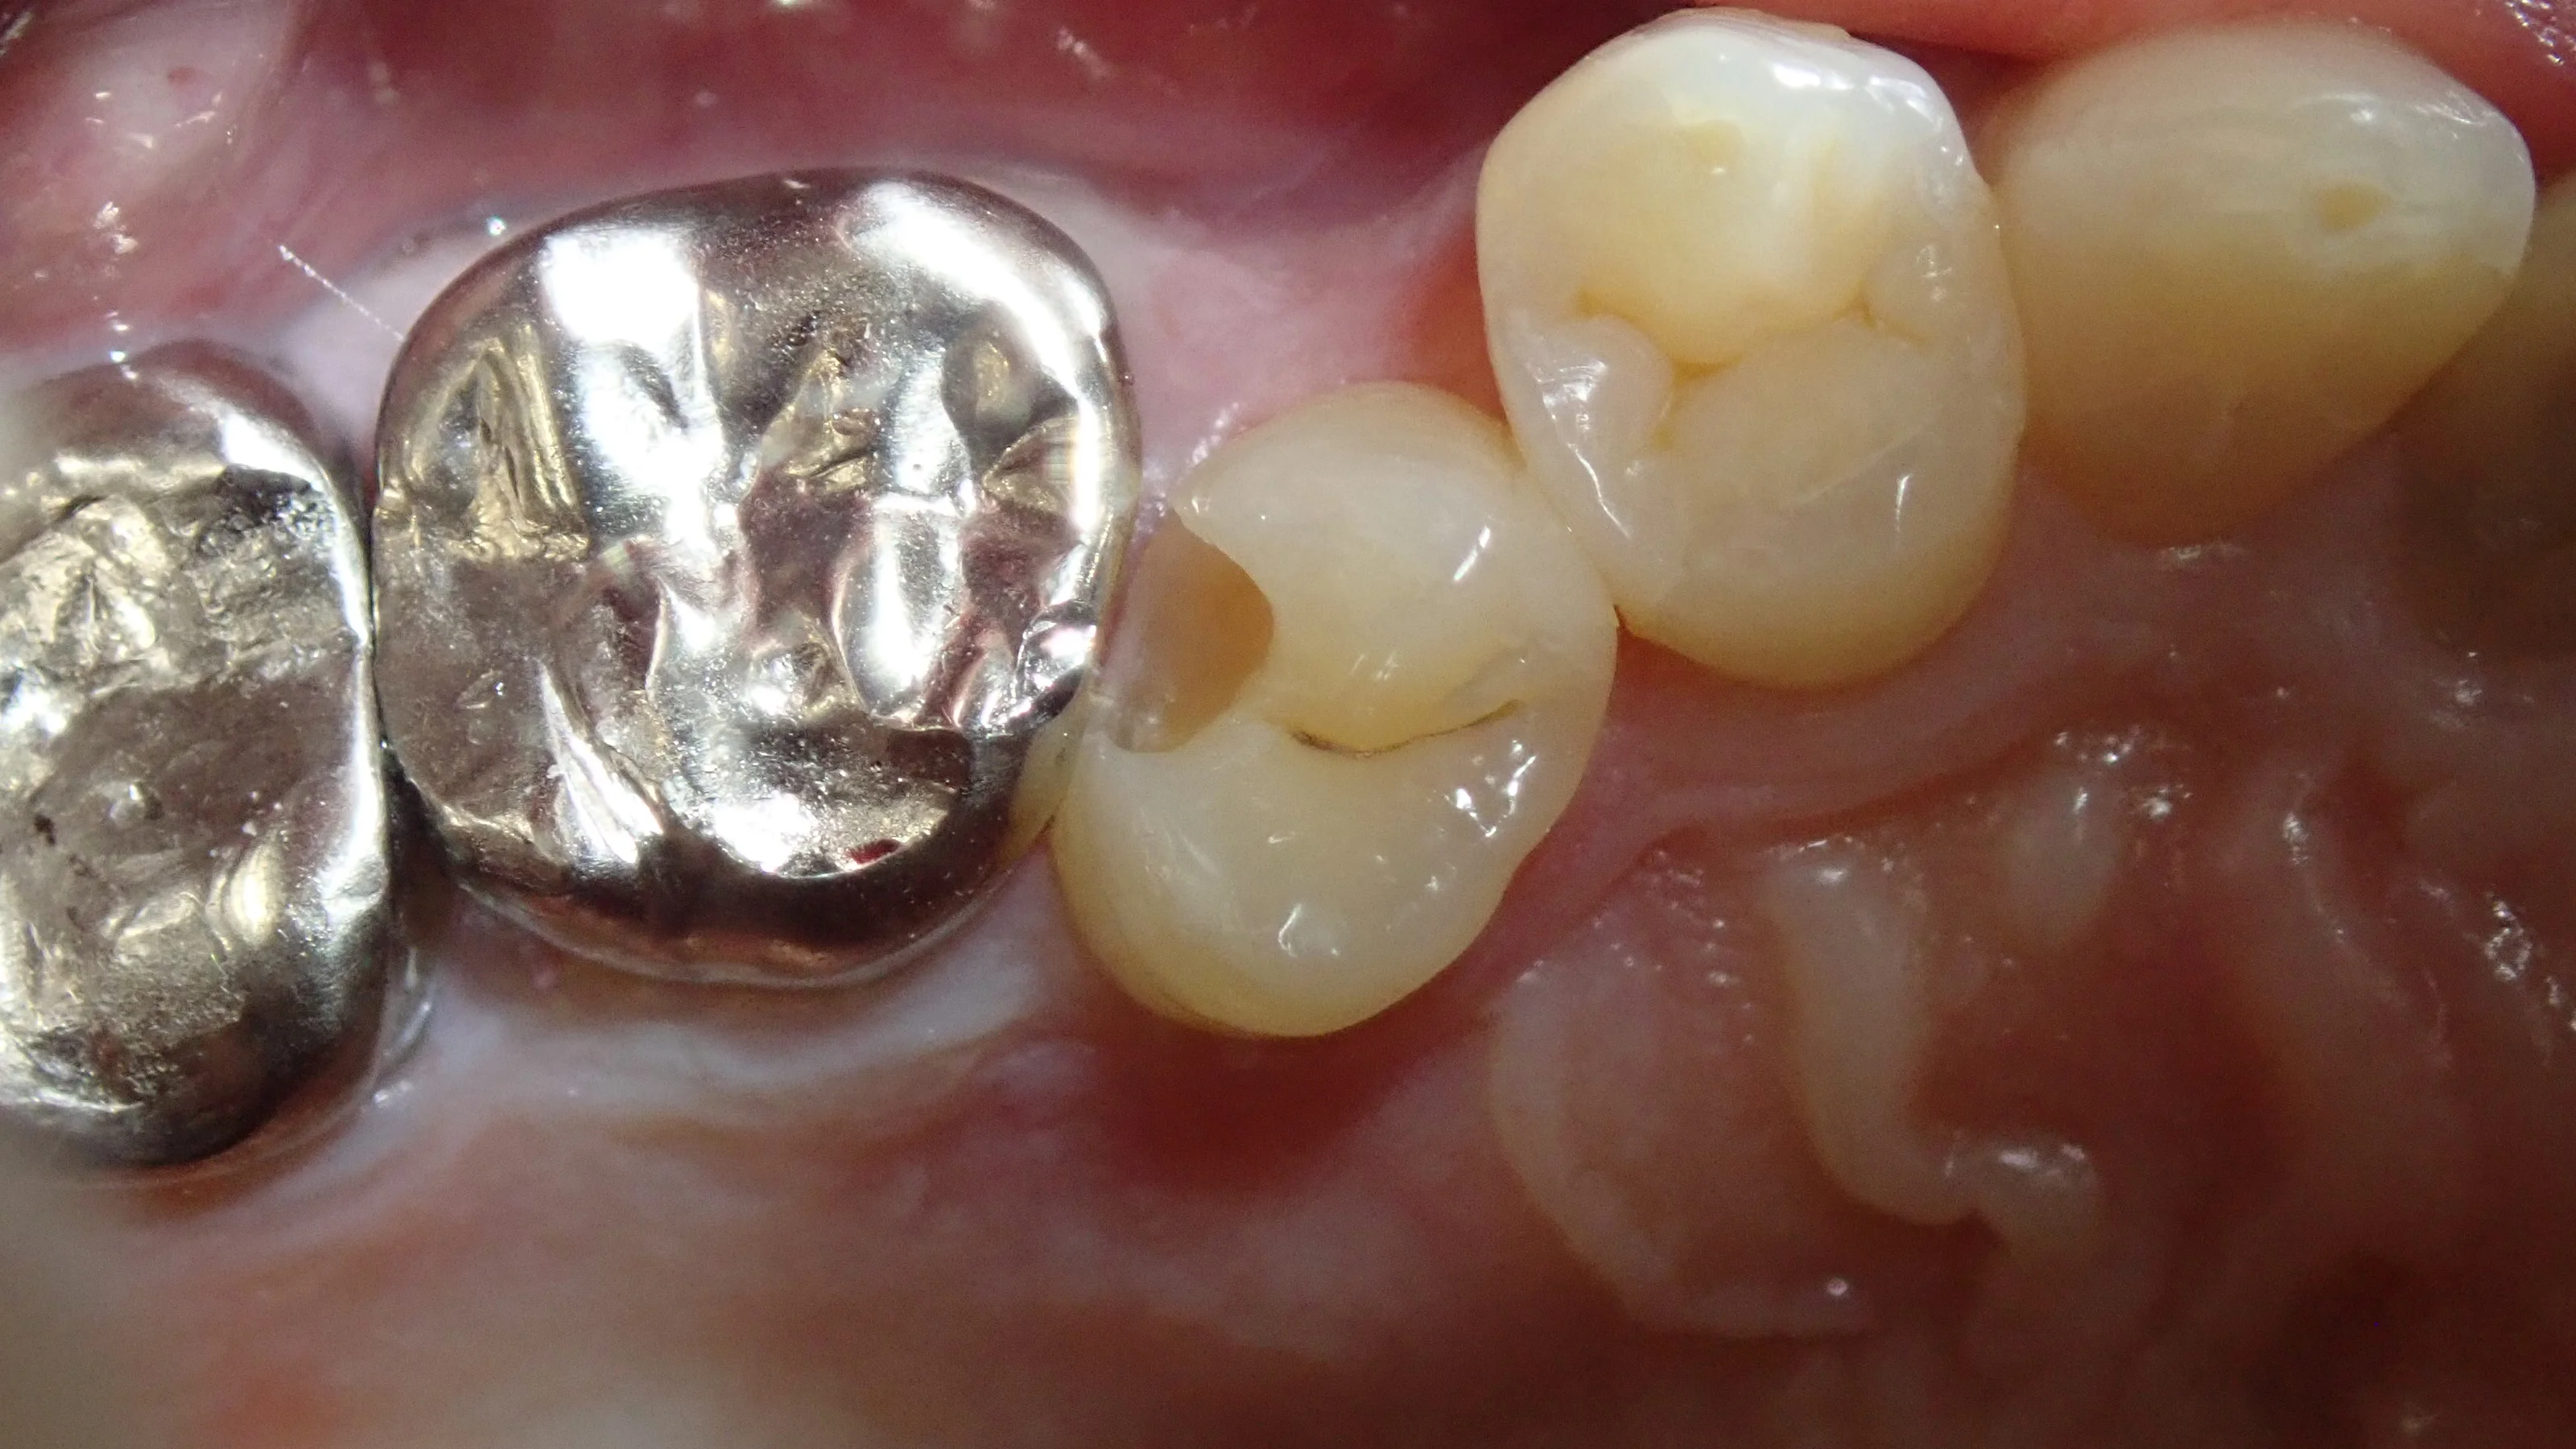

取りきったのがこちらです。

真ん中の歯は神経ギリッギリになってしまっていましたね・・・。

左側の歯に関しては、少し前のQ&Aで書きましたが・・・

麻酔が効ききる前に施術に入ってしまい、閾値が下がってしまいました・・・。

そのため、この日のこれ以上の処置が出来なくなってしまったため、虫歯を取りきらずにひとまず埋めることになってしまいました・・・施術を2回に分けることになってしまい、申し訳ありません。